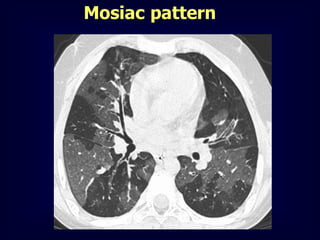

Mosiac pattern

Where is the pathology ???????

in the areas with increased density

meaning there is ground glass

in the areas with decreased density

meaning there is air trapping

Pathology in black areas

Airtrapping: Airway

Disease

Bronchiolitis obliterans (constrictive bronchiolitis)

idiopathic, connective tissue diseases, drug reaction,

after transplantation, after infection

Hypersensitivity pneumonitis

granulomatous inflammation of bronchiolar wall

Sarcoidosis

Asthma / Bronchiectasis / Airway diseases

Airway Disease

what you see……

In inspiration

sharply demarcated areas of seemingly increased

density (normal) and decreased density

demarcation by interlobular septa

In expiration

„black‟ areas remain in volume and density

„white‟ areas decrease in volume and increase in

density

INCREASE IN CONTRAST

DIFFERENCES

AIRTRAPPING

Mosaic Perfusion

Chronic pulmonary embolism

LOOK FOR

Pulmonary hypertension

idiopathic, cardiac disease, pulmonary

CTEPH =

Chronic thrombembolic